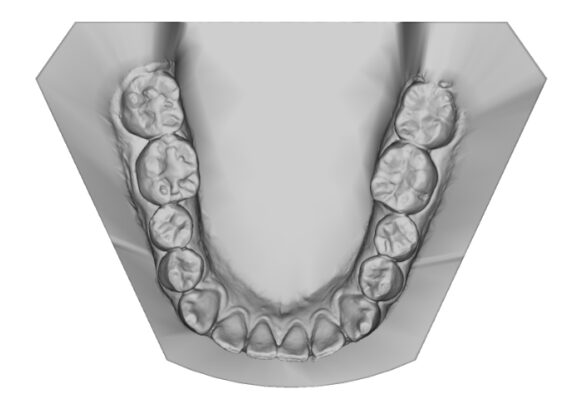

El escaneo dental es un dispositivo digital utilizado para capturar impresiones tridimensionales de la boca del paciente.

Este tipo de escaneo permite recrear la dentadura con una precisión que supera con mucho las muestras tomadas con materiales de impresión tradicionales.

• Réplica exacta de las estructuras dentales y tejidos adyacentes del paciente.

• Los escaneos son considerados tan precisos si no más exacto que los moldes de yeso. El proceso de escaneo es más cómodo para pacientes especialmente con reflejo nauseoso.